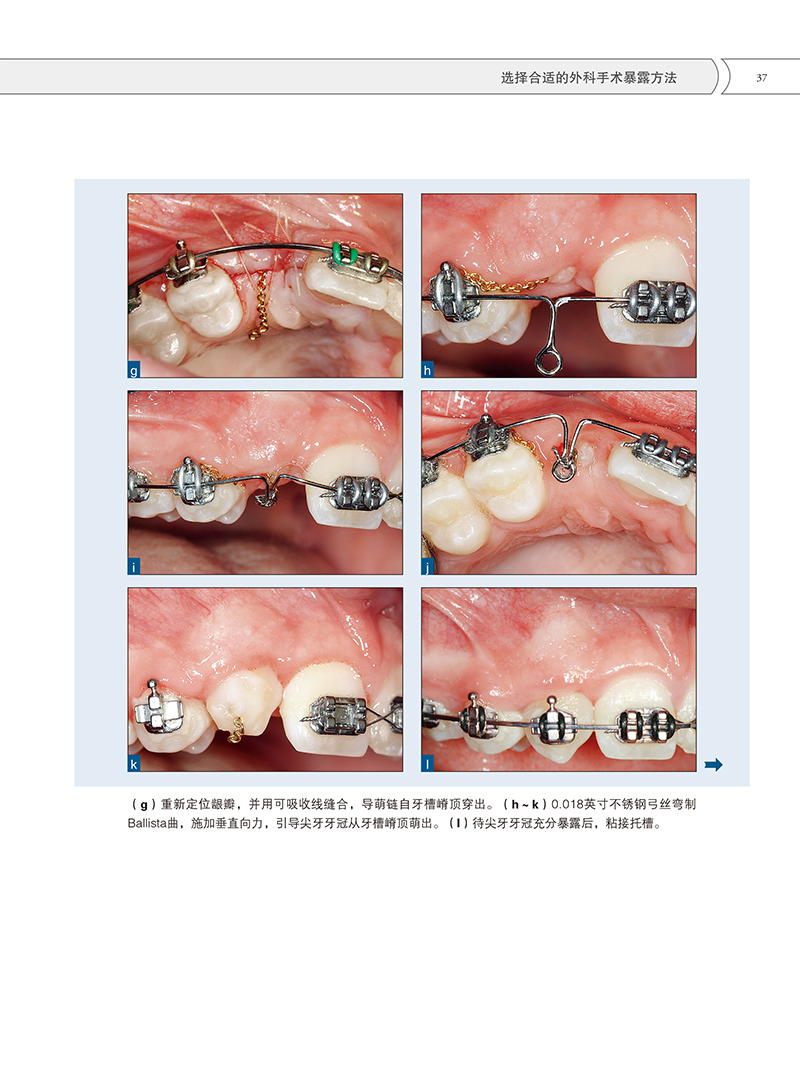

世界頂尖的正畸醫生與牙周醫生團隊近40年的經驗累積,涵蓋了各種類型的牙齒阻生,包括上頜中切牙、上頜尖牙(脣齶側阻生)、下頜尖牙、前磨牙以及下頜磨牙。每個章節關注一種類型的阻生牙,介紹瞭如何通過外科手術暴露及正畸治療牙齒。

本書是世界頂尖的正畸醫生與牙周醫生團隊近40年的經驗累積,涵蓋了各種類型的牙齒阻生,包括上頜中切牙、上頜尖牙(脣齶側阻生)、下頜尖牙、前磨牙以及下頜磨牙。每個章節關注一種類型的阻生牙,介紹瞭如何通過外科手術暴露及正畸治療牙齒。同時,本書最後一章展示了一些失敗病例,提出了相關問題,以及如何預防這些問題帶來的不良後果。